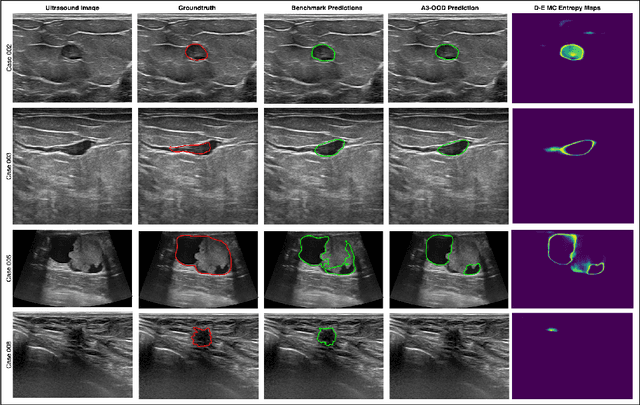

Abstract:Automated segmentation of BUS images is important for precise lesion delineation and tumor characterization, but is challenged by inherent artifacts and dataset inconsistencies. In this work, we evaluate the use of a modified Residual Encoder U-Net for breast ultrasound segmentation, with a focus on uncertainty quantification. We identify and correct for data duplication in the BUSI dataset, and use a deduplicated subset for more reliable estimates of generalization performance. Epistemic uncertainty is quantified using Monte Carlo dropout, deep ensembles, and their combination. Models are benchmarked on both in-distribution and out-of-distribution datasets to demonstrate how they generalize to unseen cross-domain data. Our approach achieves state-of-the-art segmentation accuracy on the Breast-Lesion-USG dataset with in-distribution validation, and provides calibrated uncertainty estimates that effectively signal regions of low model confidence. Performance declines and increased uncertainty observed in out-of-distribution evaluation highlight the persistent challenge of domain shift in medical imaging, and the importance of integrated uncertainty modeling for trustworthy clinical deployment. \footnote{Code available at: https://github.com/toufiqmusah/nn-uncertainty.git}